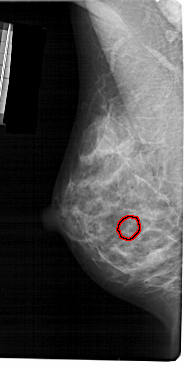

A_1392_1.RIGHT_CC

RIGHT_CC LINES 5041 PIXELS_PER_LINE 2716 BITS_PER_PIXEL 12 RESOLUTION 43.5 NON_OVERLAY

FILE: A_1392_1.LEFT_MLO.OVERLAY

TOTAL_ABNORMALITIES 1

ABNORMALITY 1

LESION_TYPE CALCIFICATION TYPE PLEOMORPHIC DISTRIBUTION CLUSTERED

ASSESSMENT 4

SUBTLETY 2

PATHOLOGY BENIGN

TOTAL_OUTLINES 1